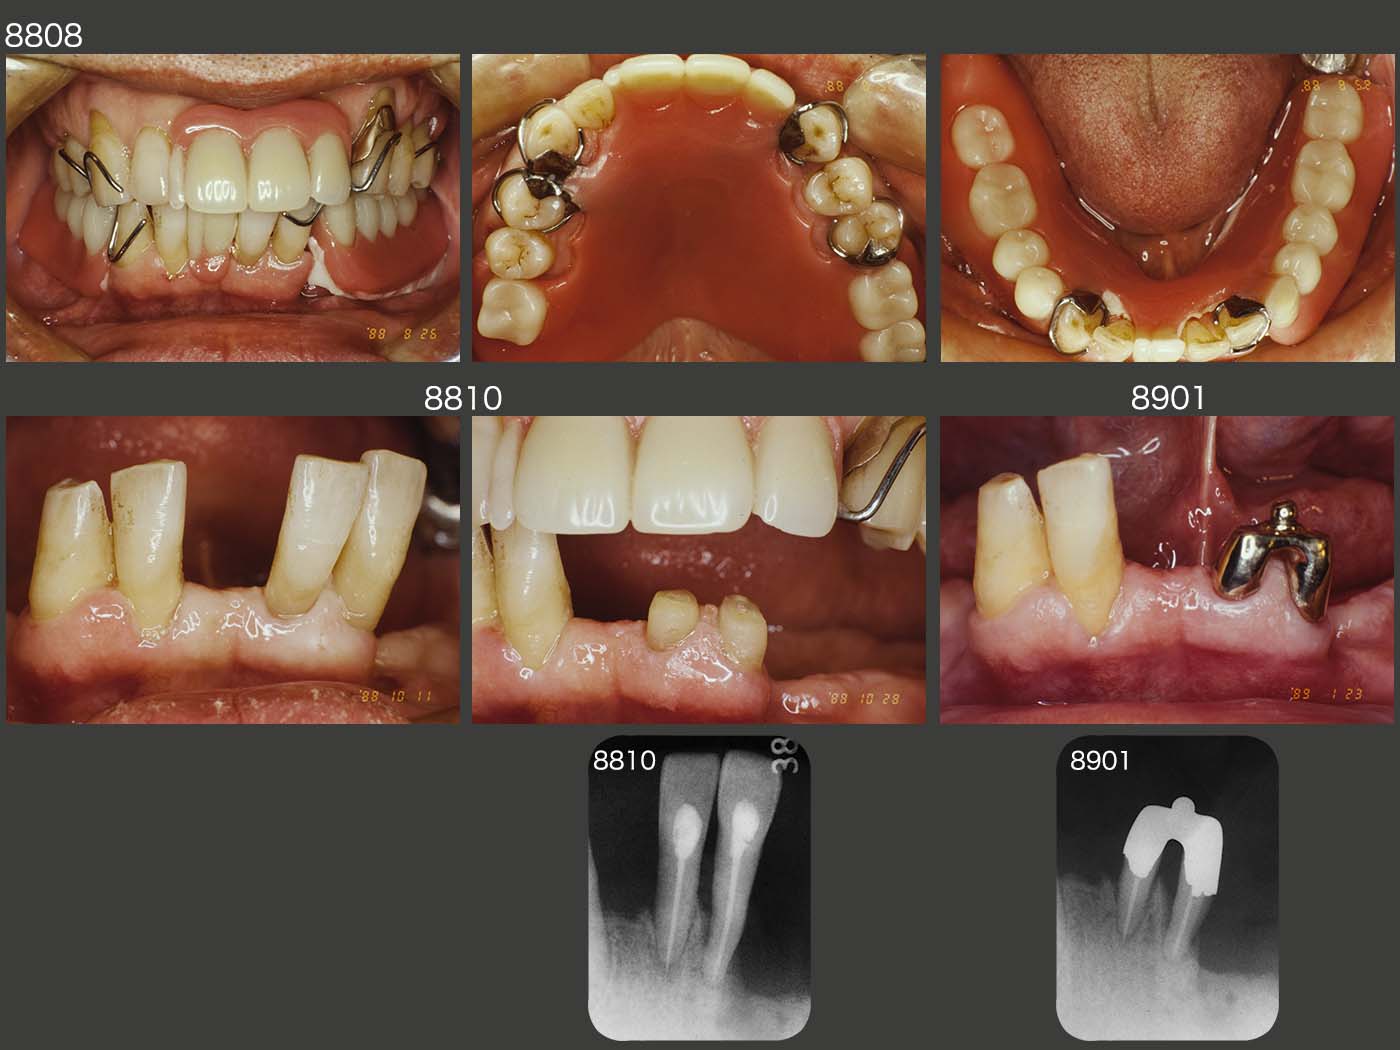

【始めにこちらをお読みください】・本商品は裁断済みです。・スキャン目的のため、1ページずつバラバラの状態になっています。・裁断済みのためやや傷や汚れありのコンディションにしていますが、中のページにつきましては、書き込みや大きな汚れはなく、比較的良好な状態です。・裁断済みであることをご理解のうえ、ご購入をお願いいたします。・裁断済みを理由とした返品はご容赦ください。・まとめ買いご希望の方はお気軽にご申請下さい。長期症例に基づいたパーシャルデンチャーの包括的医療における重要性を解説した一冊。- 出版社: クインテッセンス出版定価(本体12,000円+税)ご覧いただきありがとうございます。